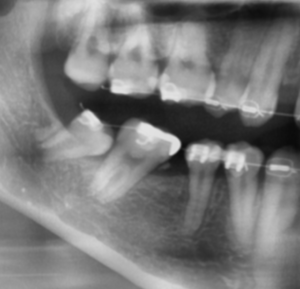

当院の親知らず抜歯前(掲載許可はいただいております)

当院の親知らず抜歯後(掲載許可はいただいております)